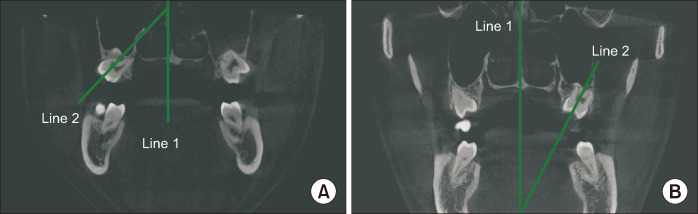

Materials and methods: : Cone-beam computed tomography (CBCT) images of 384 impacted maxillary third molars from 277 patients who visited Dankook University Dental Hospital between March 2021 and February 2024 were analyzed. The teeth were classified according to Archer's Classification (depth and axis), and the long axis angles of the maxillary first, second, and third molars as well as root involvement with the maxillary sinus were measured. Statistical analyses were conducted using the Mann-Whitney U test, chi-square test, and logistic regression analysis, with a significance level set at 0.05.

Results: : Depth categories B and C, and axis categories mesial and vertical were the most prevalent, with no significant differences in distribution based on sex (P>0.05). A significant negative correlation was found, indicating that as the buccal inclination of the maxillary second molar increased, the impacted maxillary third molar tended to incline more palatally (Kendall's tau-b=-0.245, Spearman's rho=-0.353, P<0.001). Root involvement with the maxillary sinus was not significantly associated with depth in Archer's Classification but showed a statistically significant difference based on axis (P=0.002).